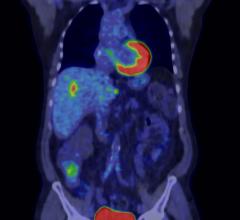

Nuclear imaging, also called molecular imaging, includes positron emission computed tomography (PET) and single photon emission computed tomography (SPECT) imaging. This section includes radiopharmaceuticals and tracers, PET-CT, SPECT-CT, and PET-MRI. Molecular imaging includes the field of nuclear medicine, which uses very small amounts of radioactive materials, or radiopharmaceuticals, to diagnose and treat disease.

Technological advancements in positron emission tomography/computed tomography (PET/CT) offer both clinicians and ...

The next generation of positron emission tomography (PET) imaging agents will herald an age when PET will eclipse single ...

Efficiency and effectiveness are inseparable in clinical medicine. Digital PET addresses them both. The key is the ...